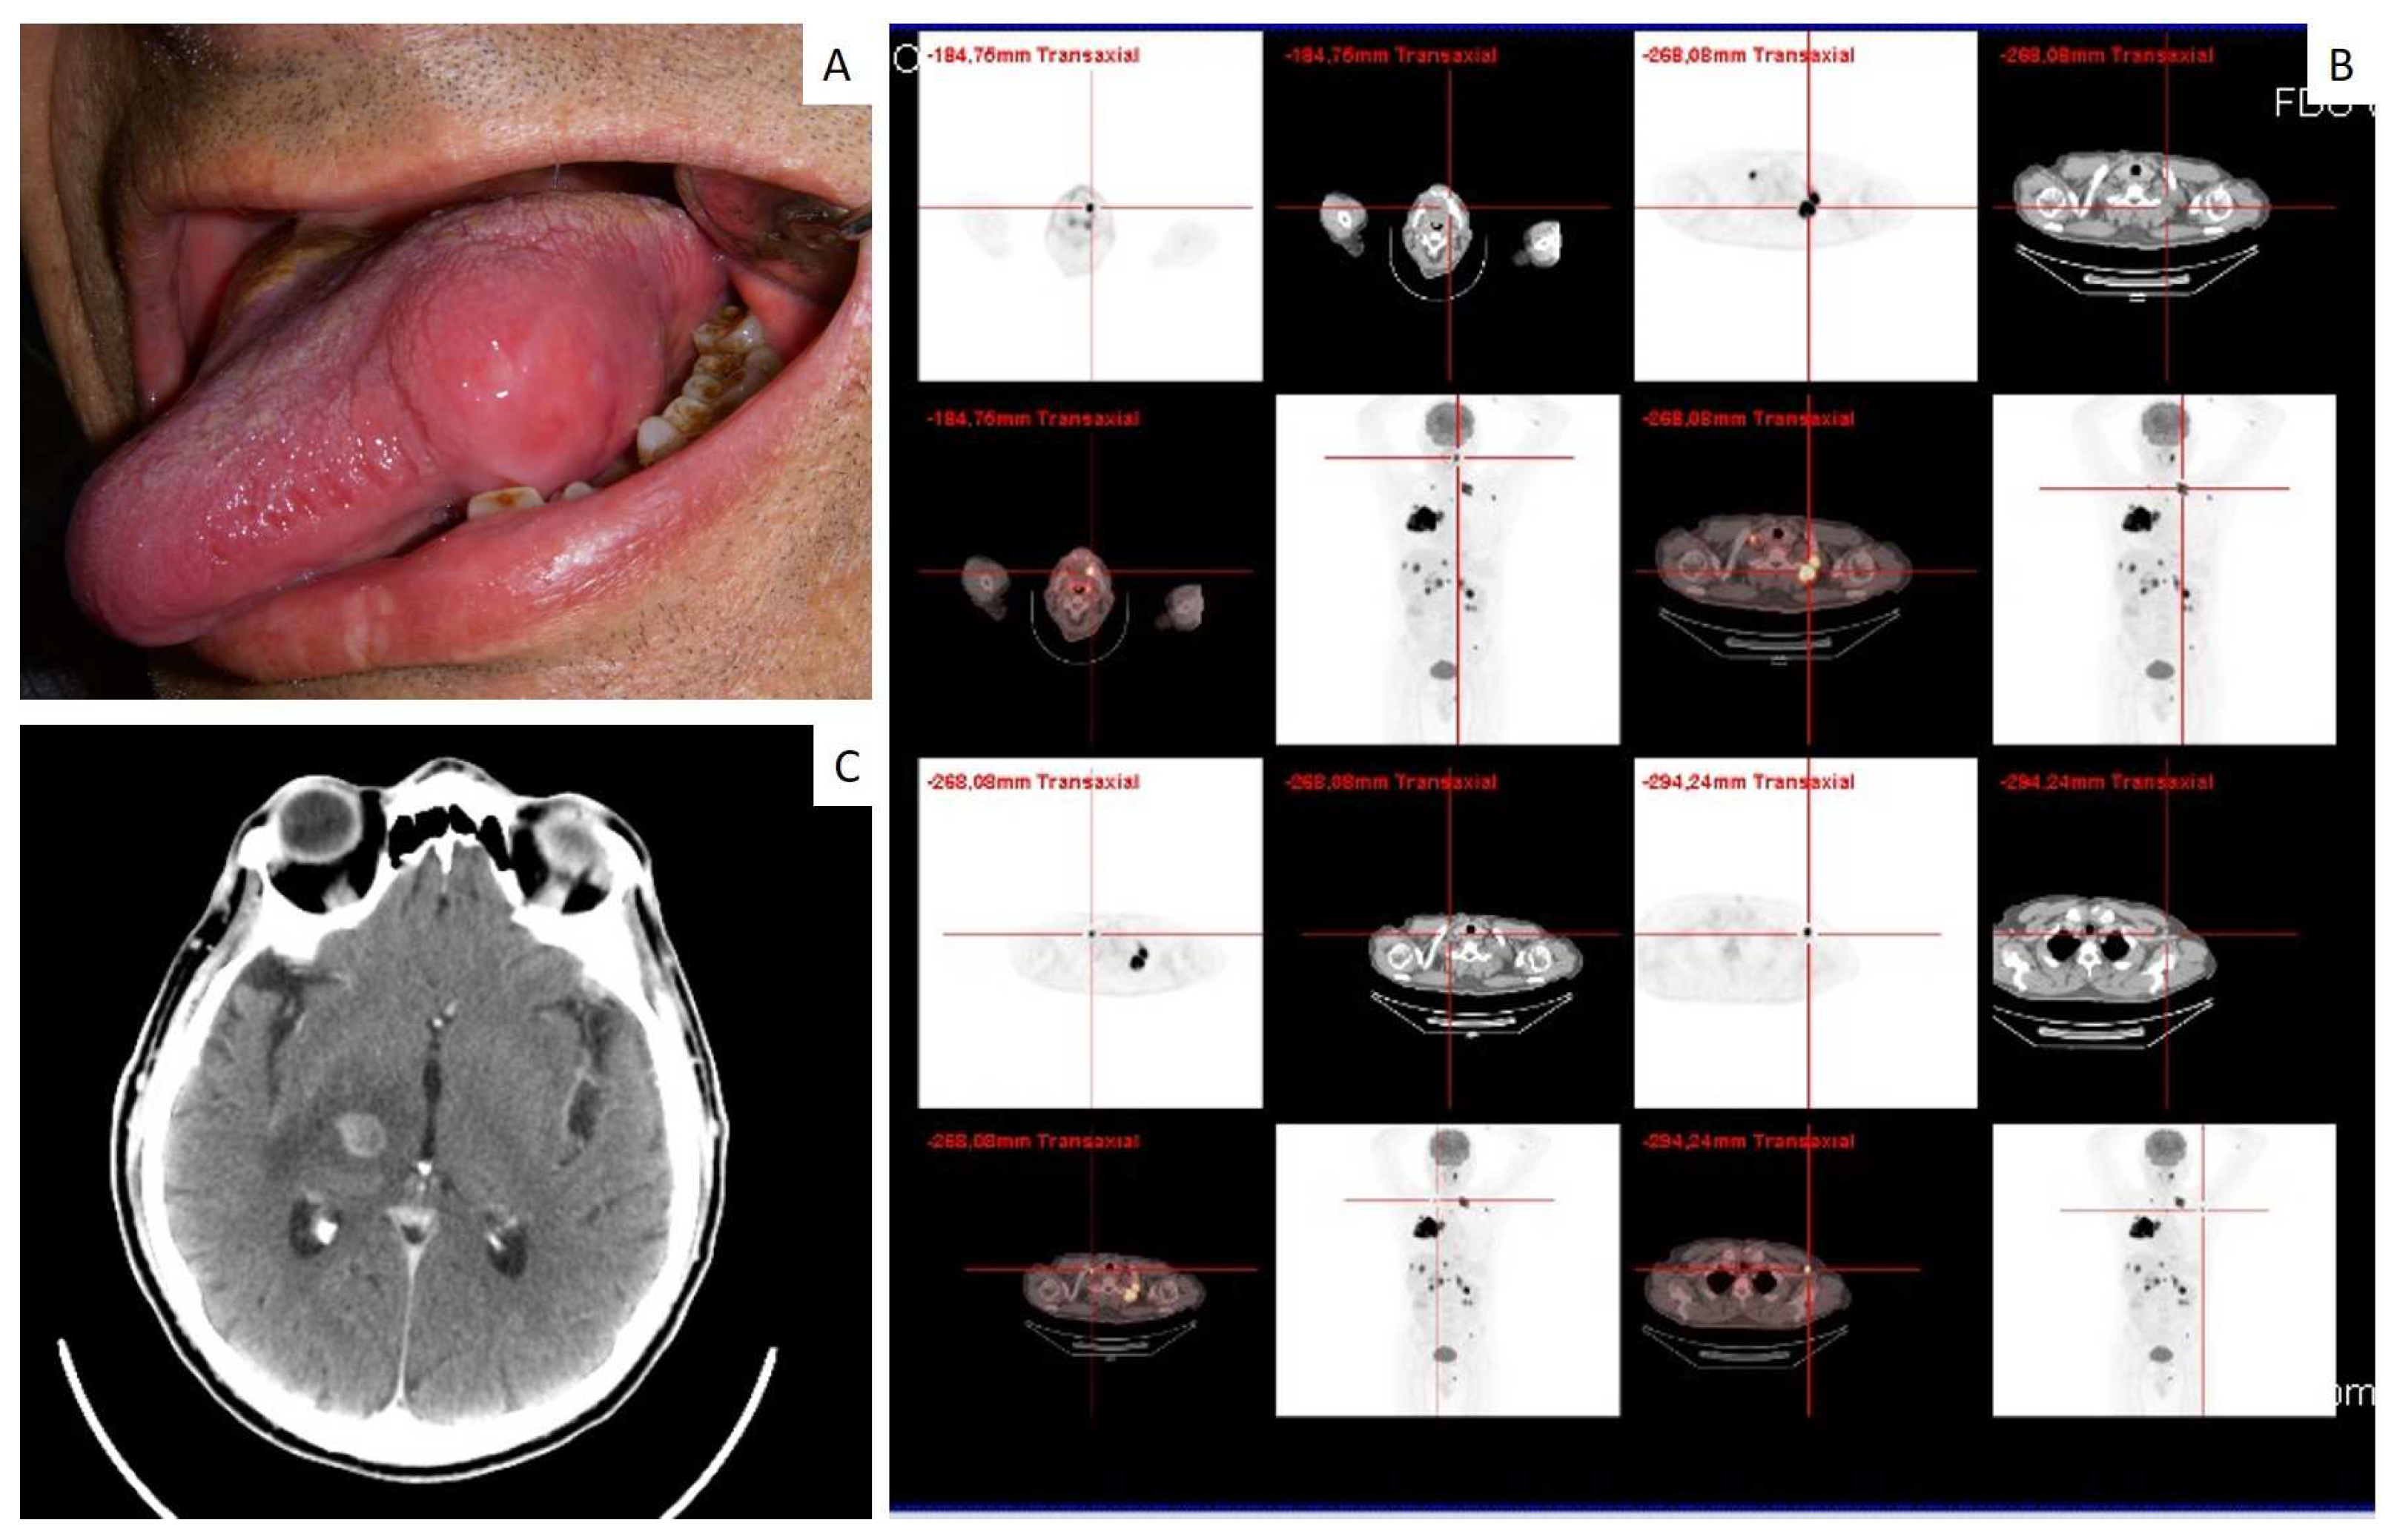

| 19 | 65 | F | Tongue | Small cell carcinoma | n.a. | Yes |

| 20 | 72 | F | Maxillary gingiva | Adenocarcinoma | n.a. | Yes |

| 21 | 66 | M | Tongue | Small cell carcinoma | Brain | No |